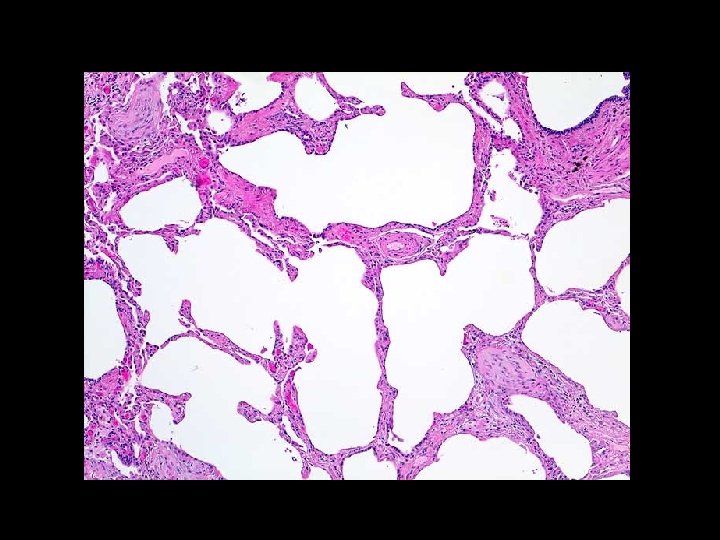

PFT Patterns § Emphysema § Chronic Bronchitis § FEV 1/FVC <70% § “Scooped” FV curve § TLC increased § TLC normal § Increased compliance § Normal compliance § DLCO decreased § DLCO usually normal